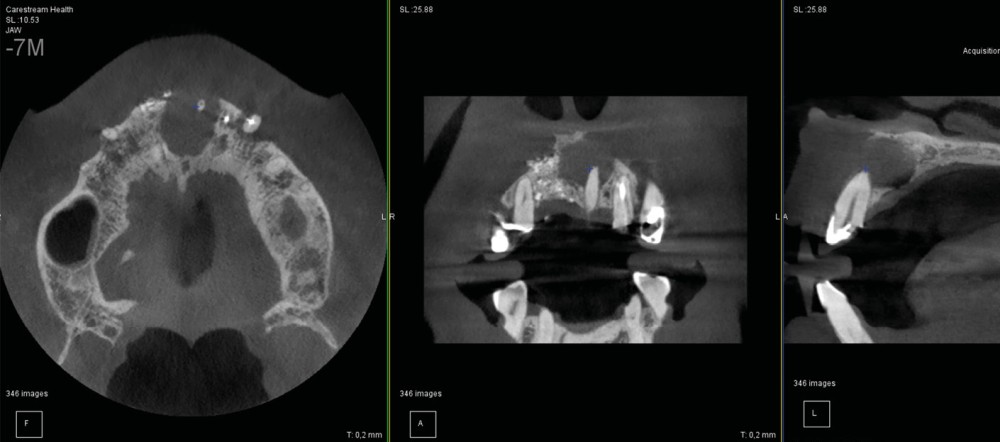

On distingue classiquement le granulome (- 1 cm) du kyste (+ 1 cm). Ce dernier possède des parois propres et des contours réguliers bien délimités. Le développement kystique s’accompagne volontiers d’un refoulement des structures avoisinantes, les corticales osseuses apparaissent soufflées, dans certains cas, amincies, pouvant venir empiéter sur des éléments anatomiques de la sphère maxillo-mandibulaire (sinus, canal mandibulaire, fosses nasales, foramen mentonnier…) (fig. 3).